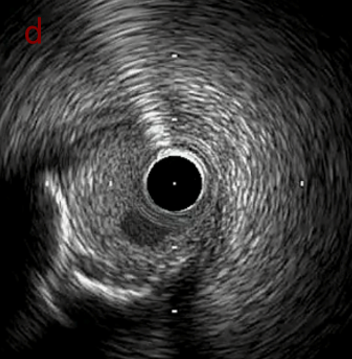

IVUS after OAS low speed 3回

IVUS imaging after low speed 3回

OAS low speedによる引きのsandingを3回行いIVUSを確認するとa-cでは心筋側側へのOASによる良好なbias変化と、それに伴いdの健常側への危険なbias変化を認めた。

そのためcでIVUSマーキングを行い、その点より引きで赤線のpinpoint OAS high speedを行い、dに関してはinjury回避のためにOASを当てない方針とした。